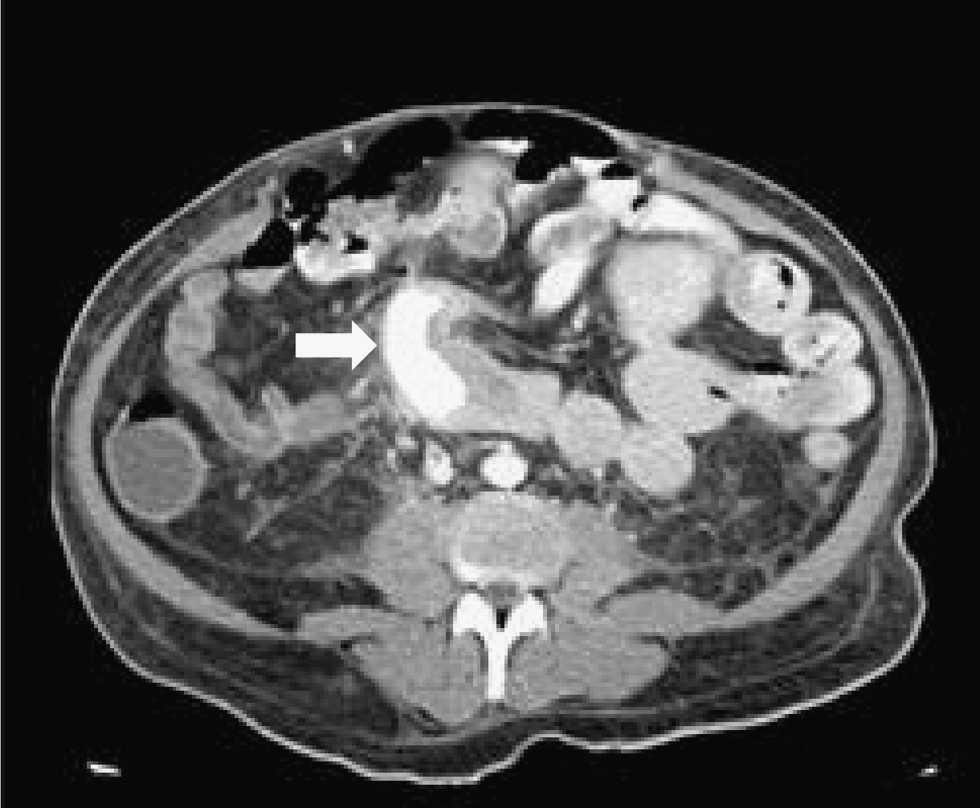

La realización de una fibrogastroscopia no mostró alteraciones significativas. Se continuó el estudio mediante la tomografía computarizada (TC) con contraste endovenoso, y se identificó un paso masivo de contraste a la luz del duodeno del injerto pancreático (figura 1). Durante la realización de la TC presentó varios episodios de enterorragias masivas y hemorragia digestiva alta.

Figura 1. Se observa la extravasación masiva del contraste endovenoso al duodeno del injerto y la presencia del contraste en asas de intestino delgado.